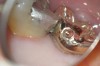

During treatment, images can be efficiently captured, shared, and stored in a patient's digital chart. This is especially useful when unforeseen issues are encountered, such as extensive decay and cracks13 (Figure 12). Images not only help to increase a patient's trust and confidence in the treating doctor, especially for newer patients, but can also aid in reducing one's medico-legal risk.12

Fig 12. DOM-acquired image showing significant crack on pulpal floor.

Figure 12